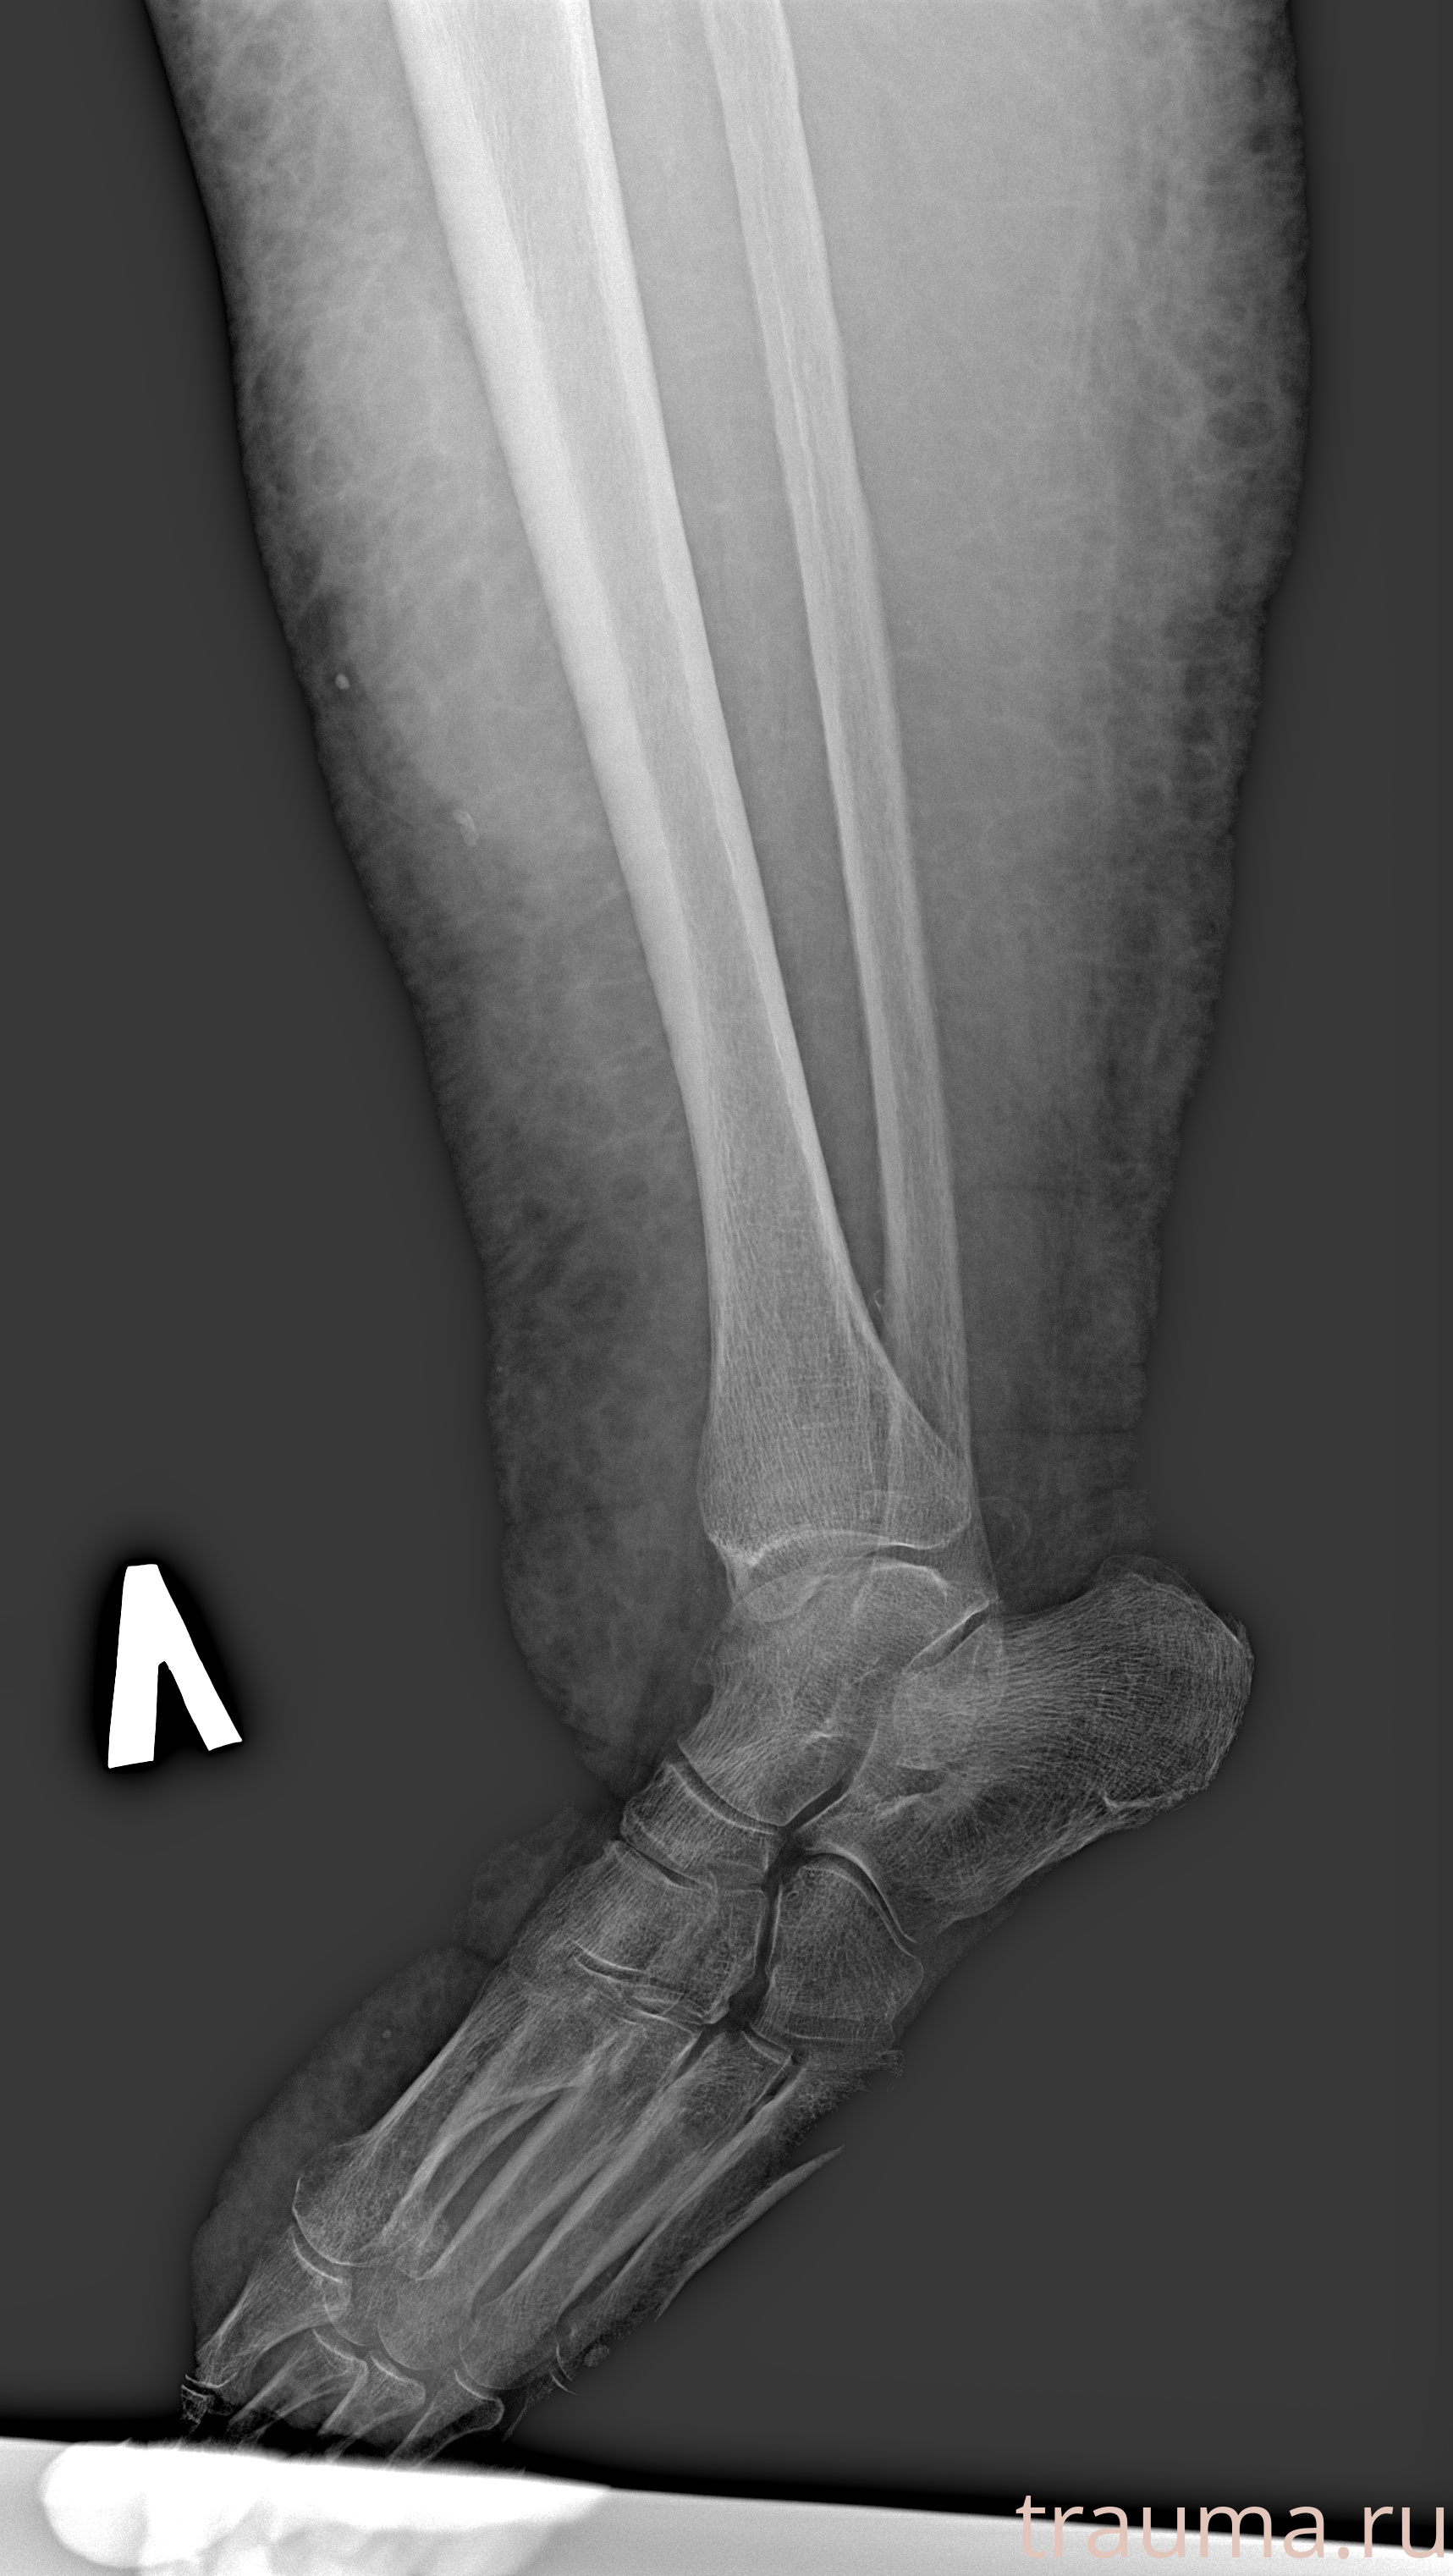

Рентгенограммы

Рентген на дому: по вашему адресу приезжает врач-рентгенолог, травматолог-ортопед с мобильным рентгеновским аппаратом, проводит диагностику травмы или заболевания, делает необходимые рентгенограммы, дает рекомендации по дальнейшему лечению. Получить качественные снимки в домашних условиях возможно благодаря уникальной методике, разработанной МосРентген Центром для института  Склифосовского